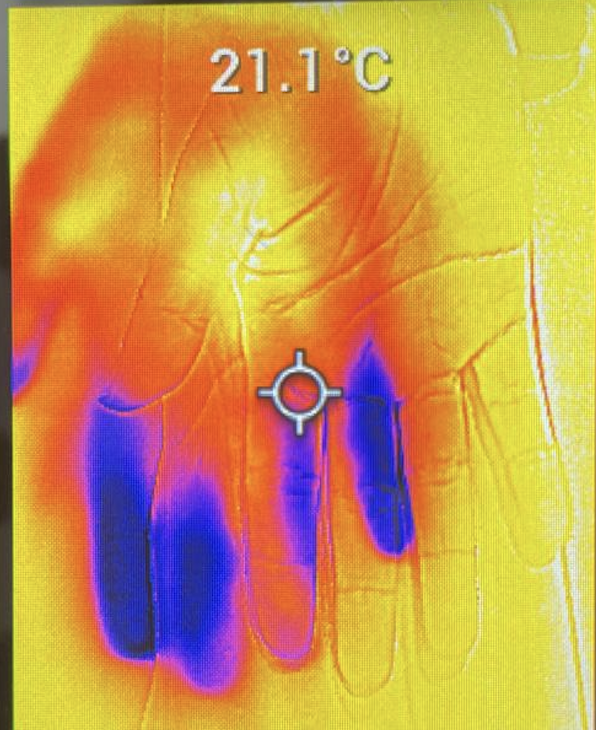

Dorso de la mano del control sano

Dorso de la mano de un paciente con Disautonomia

Palma de la mano del control sano

Palma de la mano de un paciente con disautonomía